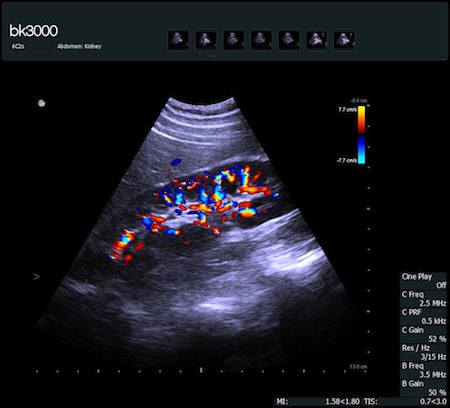

Obrazy kliniczne uzyskane aparatem bk3000

Fot. Przekrój strzałkowy prawej nerki w opcji Color Doppler uzyskany głowicą 6C2s.